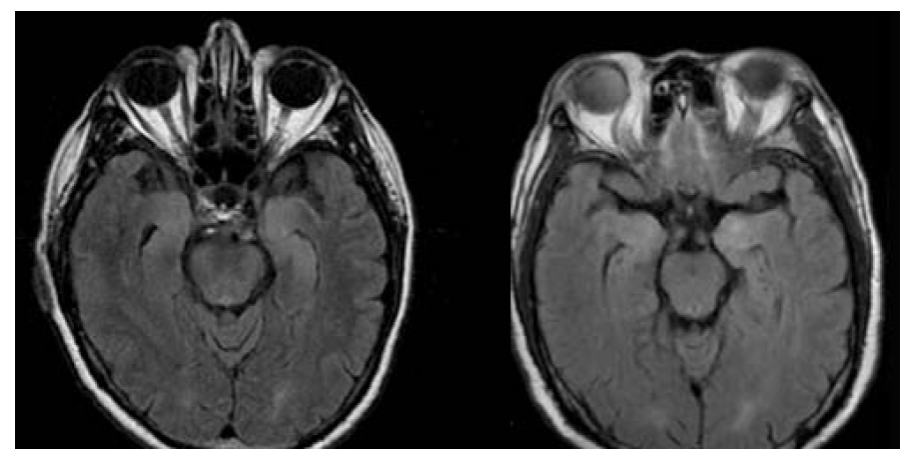

En el contexto de un cuadro clínico compatible, algunos estudios paraclínicos comúnmente disponibles pueden apoyar el diagnóstico de encefalitis anti-NMDAr. La imagen por resonancia magnética (IRM) cerebral puede demostrar hiperintensidades en la secuencia FLAIR en el lóbulo temporal medial, ínsula, tallo cerebral, ganglios basales o corteza (Figura 2). Ahora bien, hasta 50 % de los pacientes puede tener IRM normal.2

Figura 2 Imagen de resonancia magnética cerebral en secuencia T2 FLAIR con cortes axiales a nivel del lóbulo temporal medial. Se observa incremento bilateral en la intensidad de señal de las cabezas de los hipocampos. Mujer de 22 años, con diagnóstico de encefalitis anti-NMDAr definitiva.